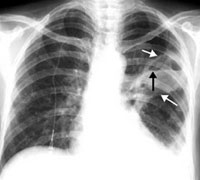

Trên phim chụp Xquang phổi có thể thấy thâm nhiễm thoáng qua, thường gặp hơn ở những vùng trên của phổi; hay thấy hình ảnh các nút nhầy là những khối mờ đồng nhất phân nhánh điển hình, hay hình ảnh “đường rail” và hình “nhẫn” là do vách phế quản dày lên. Chụp phế quản có cản quang hoặc chụp cắt lớp vi tính có thể xác định giãn phế quản trung tâm đặc trưng của bệnh. Xét nghiệm máu thấy tăng bạch cầu đa nhân ái toan. Ở những nút nhầy do bệnh nhân khạc ra có màu nâu nhạt, nếu nhuộm soi sẽ thấy nhiều bạch cầu đa nhân ái toan và các thành phần sợi nấm. Nếu cấy đàm thấy nấm phát triển 60 - 100%. Bệnh nhân có biểu hiện mẫn cảm da tức thì (type I) và muộn (type III) đối với kháng nguyên Aspergillus từ 87 - 100%. Chức năng phổi bị suy giảm: có tắc nghẽn khí đạo; hội chứng hạn chế, giảm khả năng khuếch tán CO2 xuất hiện khi bệnh kéo dài. Các nhà chuyên môn nêu ra 4 dấu hiệu chủ yếu để chẩn đoán ABPA là: có hình ảnh thâm nhiễm trên phim Xquang lồng ngực tái phát nhiều lần; tăng bạch cầu đa nhân ái toan trong máu hoặc đàm; hen phế quản; sự mẫn cảm da tức thì và trễ đối với các kháng nguyên Aspergillus.